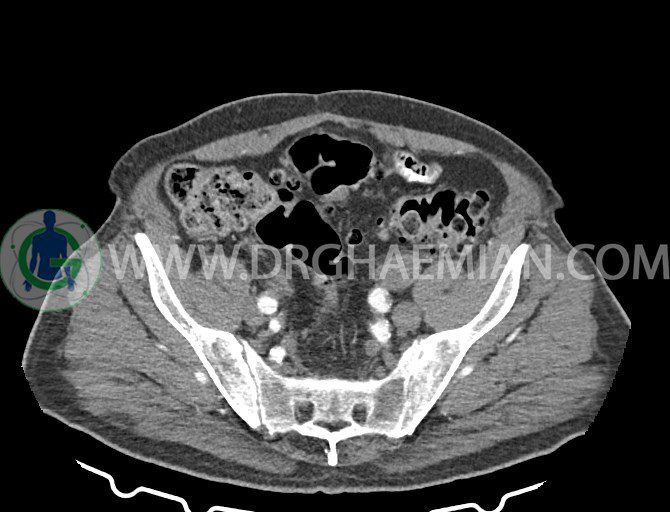

سی تی اسکن لگن یکی از روش های تصویربرداری با سی تی اسکن است. این روش با استفاده از تشعشعات تصاویر عرضی از ناحیه شکمی ایجاد میکند. در این کیس ديورتيكولوزيس، کیست های کورتیکال در هر دو کلیه، لنفادنوپاتی، کلسیفیکاسیون دیواره آئورت و شریان ایلیاک، تغییرات DJD ناحیه توراکولومبار و پروستات بزرگتر از عادی دیده می شود.

در سي تي اسکن اسپيرال شکم و لگن با و بدون کنتراست خوراکی و وريدی (مولتي ديدکتور 16 با مقاطع ظريف و بازسازي هاي ساژيتال و کرونال):

– کلسيفيکاسيون ديواره آئورت و شريان ها ايلياک همراه با نشانه هاي ترومبوز مورال در بيفورکاسيون ائورت با امتداد به پروگزيمال هاي شريان هاي ايلياک

لنفادنوپاتي به ابعاد mm 22 x 25 مجاور شريان ايلياک خارجي چپ و به ابعاد mm 17 x 28 مجاور شريان ايلياک خارجي راست

– پروستات به ابعاد mm 45 x 54، بزرگ تر از نرمال